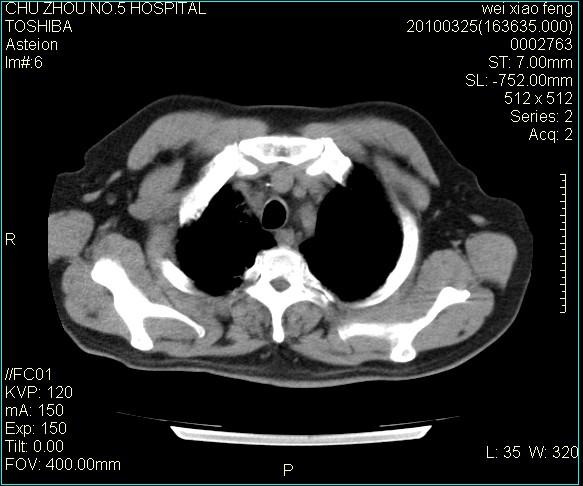

男,60岁,反复咳、痰、喘3月,加重3天。

双肺间质性改变。

考虑双肺血型潘散肺结核/

间质性肺炎伴间质纤维化!不排除伴有职业病!

双肺间质纤维化,双肺血型潘散肺结核。

考虑间质性肺炎伴间质纤维化。

右肺中叶结节影为原发灶,考虑右肺中叶周围型肺癌并淋巴道转移